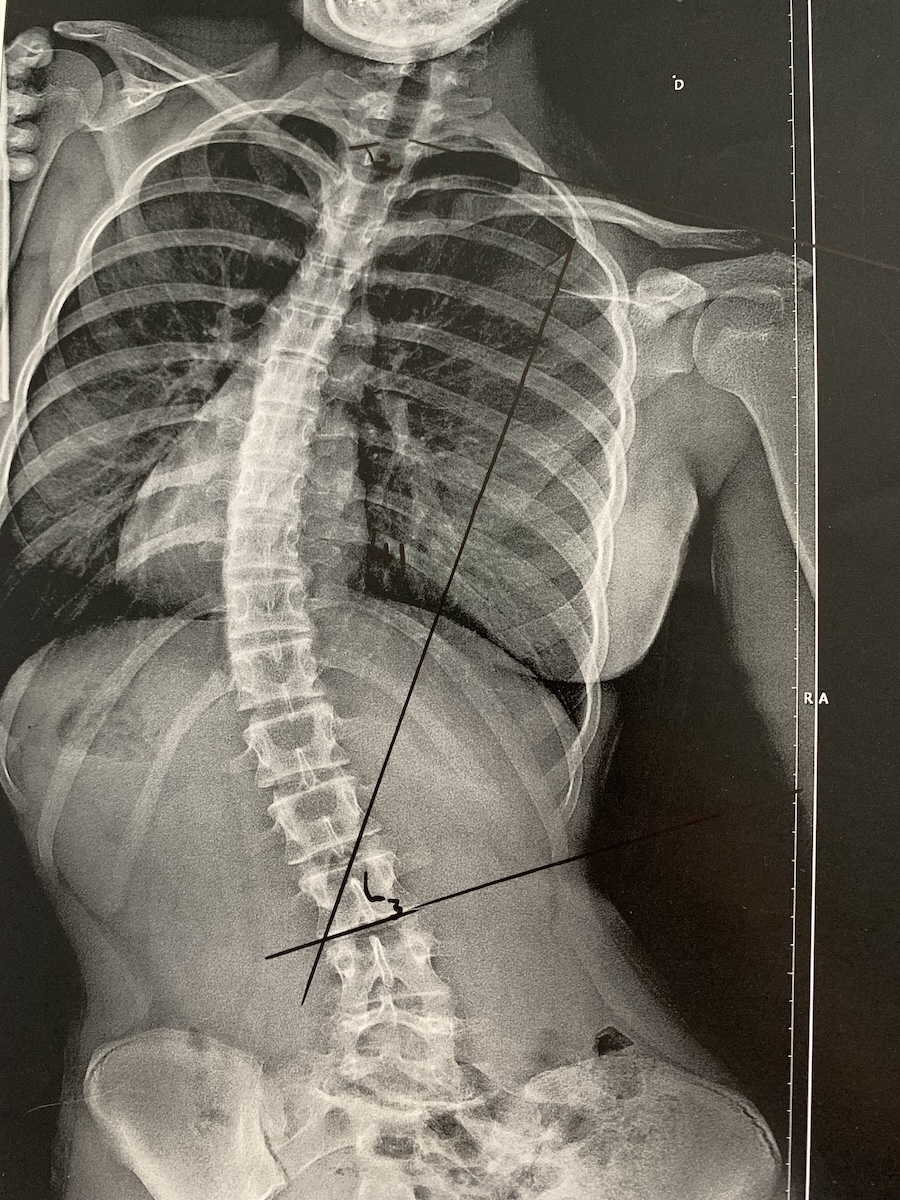

Un jour, à 15 ans, elle découvre qu’une maladie tord son corps et le soumet à de multiples douleurs : cette maladie, encore méconnue du grand public, s’appelle les troubles neurologiques fonctionnels (TNF, en anglais : FND).

Avant, Mélina était une ado de 15 ans comme les autres. Après, il y a ce corps étrangement tordu, ces douleurs inexplicables. Un basculement dans une autre vie, qui ne fracasse pas seulement le corps de Mélina Gentas.